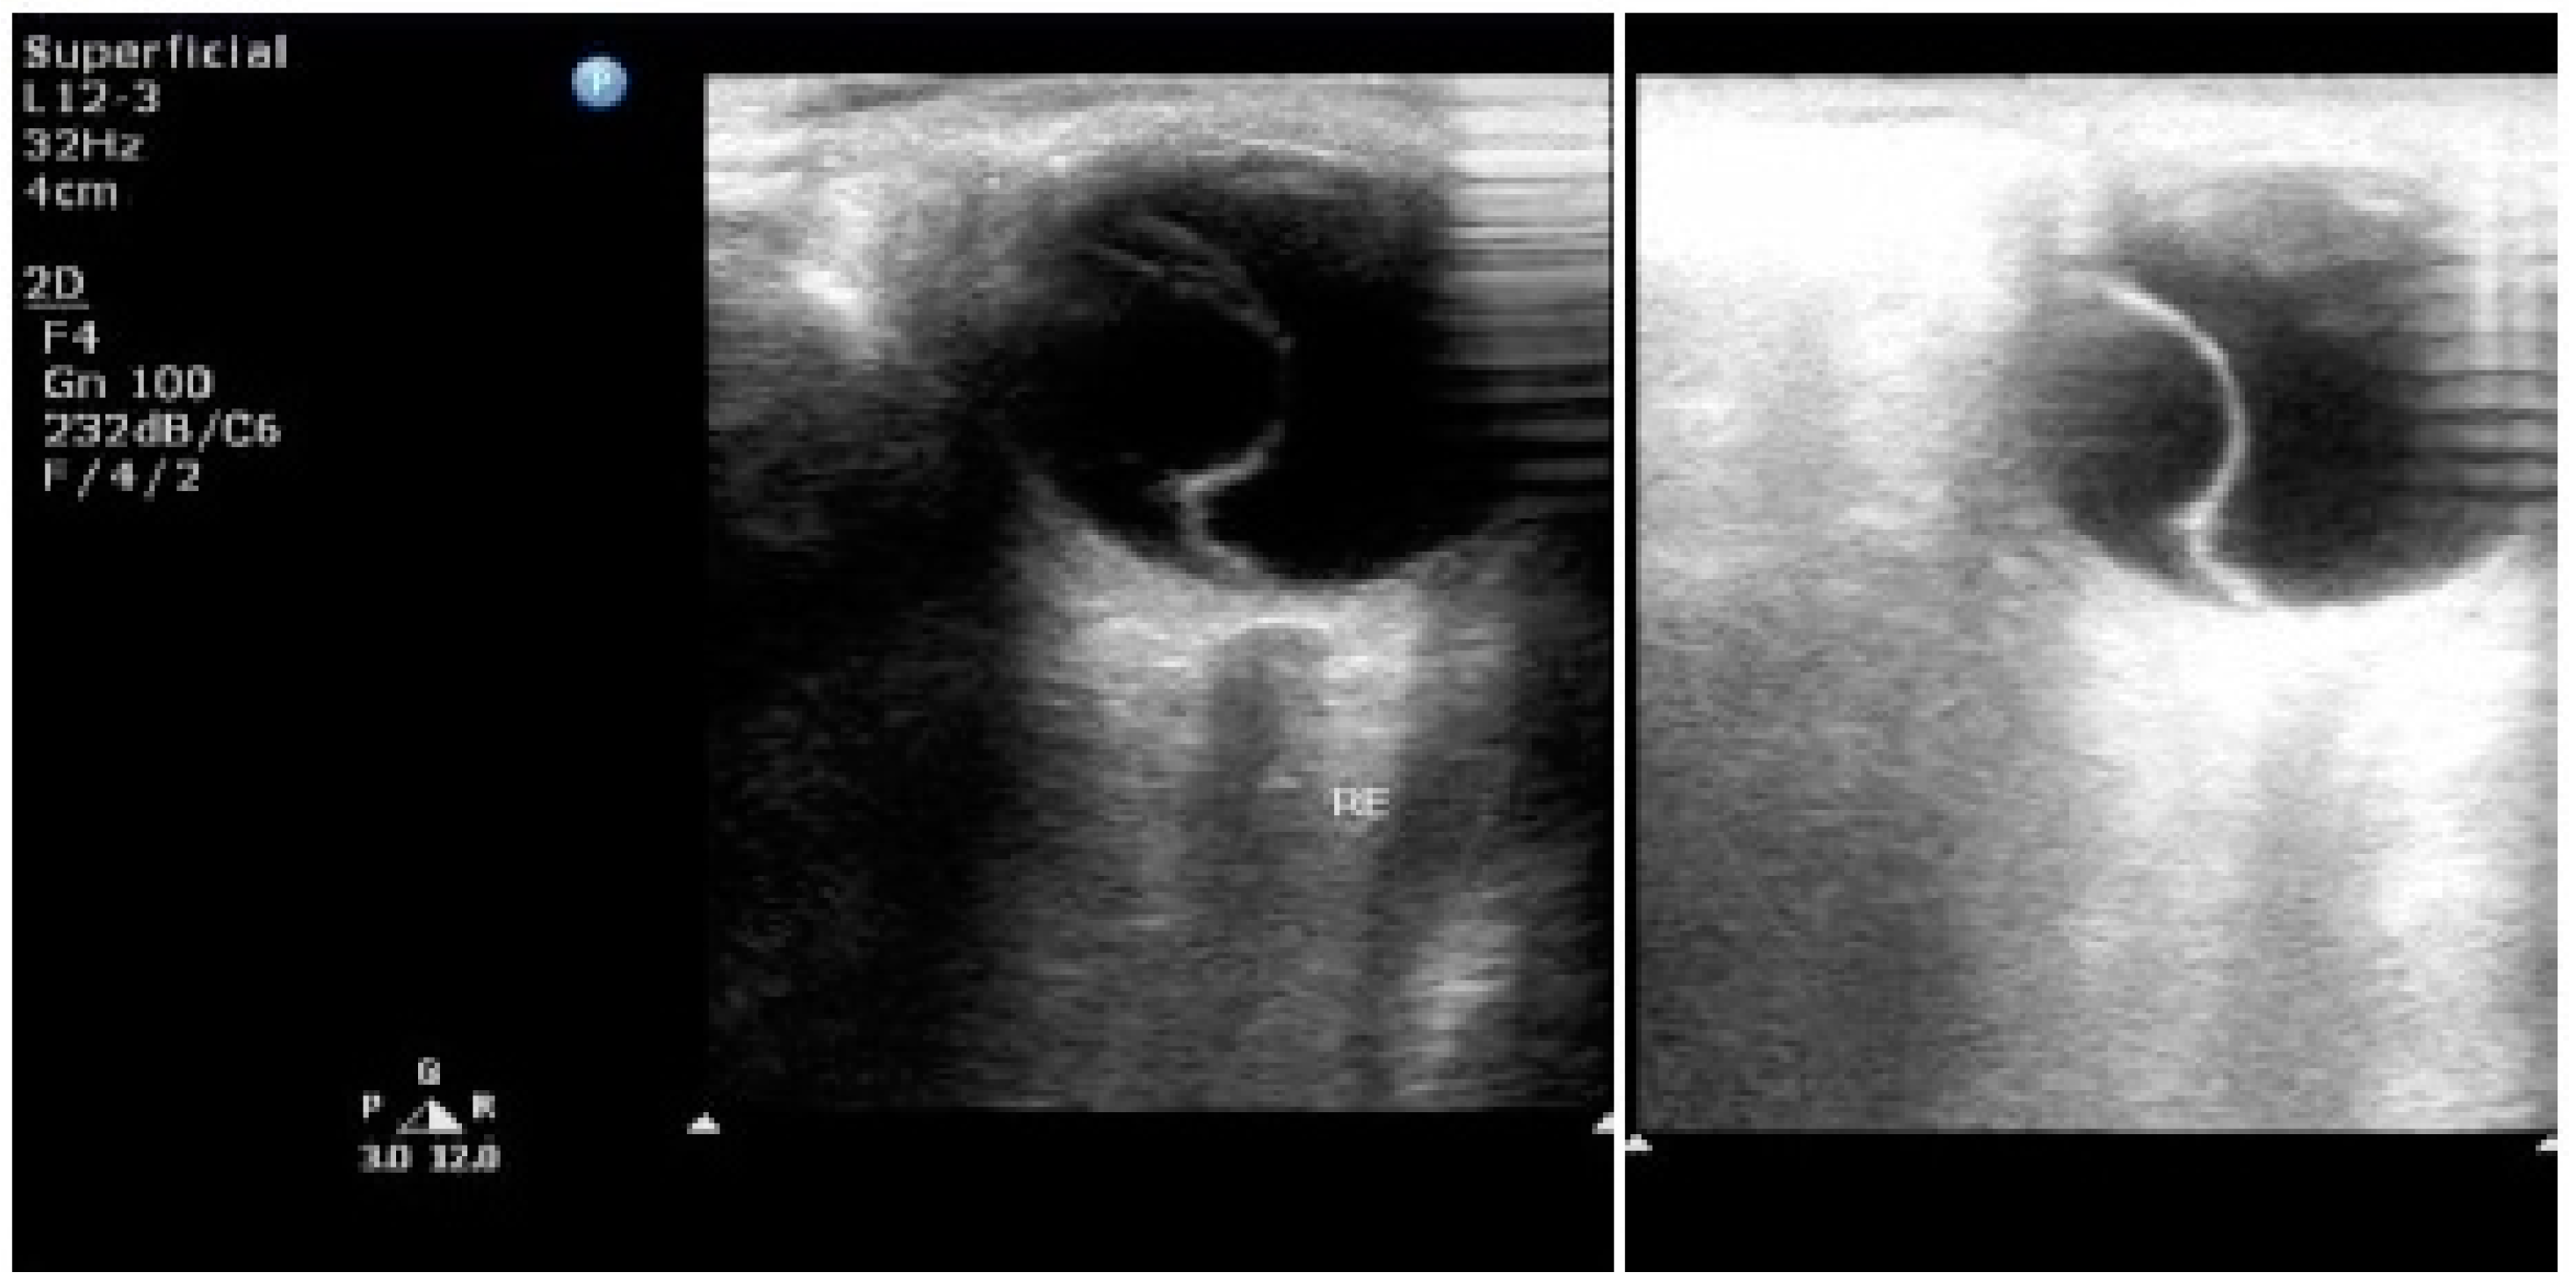

7. Ultrasonography

- Fledelius, H.C. Ultrasound in ophthalmology. Ultrasound Med. Biol. 1997, 23, 365–375. [Google Scholar] [CrossRef]

- Sconfienza, L.M.; Lacelli, F.; Ardemagni, A.; Perrone, N.; Bertolotto, M.; Padolecchia, R.; Serafini, G. High-resolution, 3-D, and contrast-enhanced ultrasonographic findings in diseases of the eye. J. Ultrasound 2010, 13, 143–149. [Google Scholar] [CrossRef] [PubMed][Green Version]